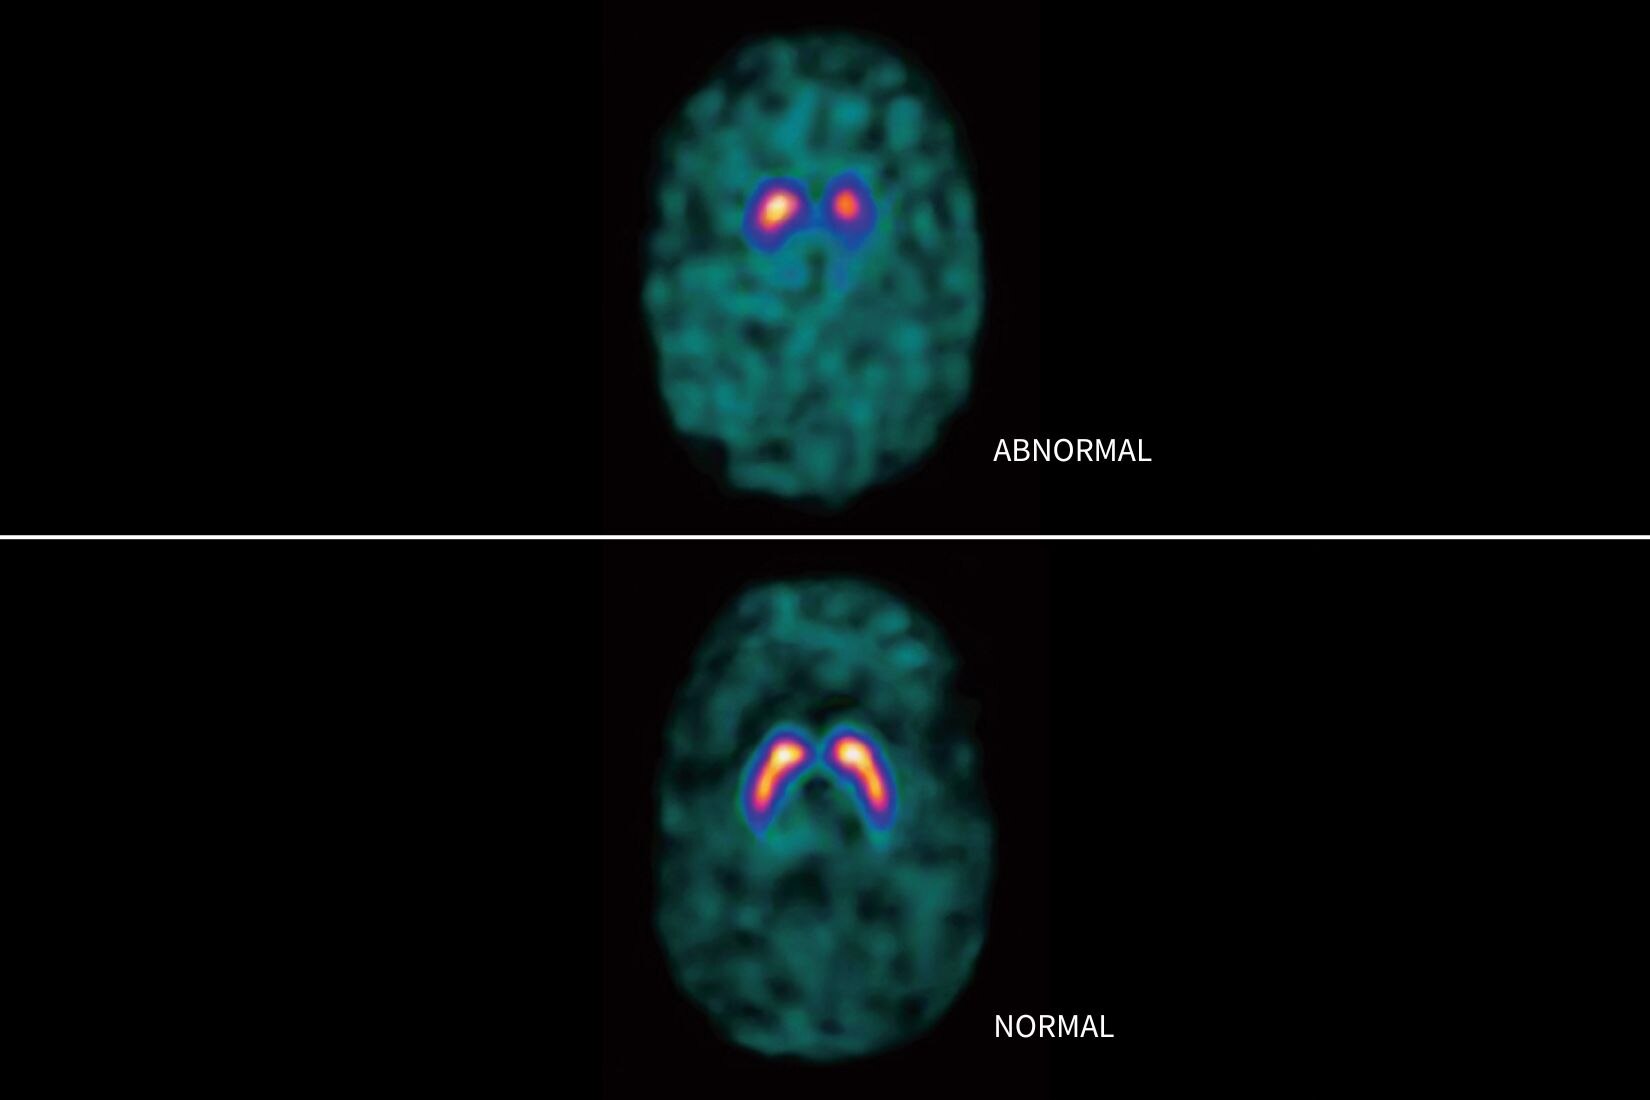

EXCELLENCE CLINIQUE